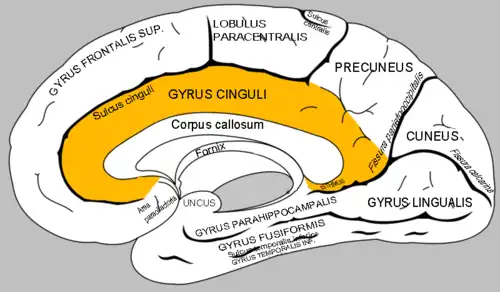

Gyrus cinguli

(der Gyrus cinguli, der relativ zentral liegt, ist orange hervorgehoben)

Der Gyrus cinguli[1] (von lateinisch gyrus ‚Windung‘ und cingulum ‚Gürtel‘) oder Gürtelwindung ist ein Teil des Gehirns und gehört funktionell zum limbischen System. Es handelt sich um eine Struktur des Telencephalons (Endhirn), oberhalb des Corpus callosum (Balken), die die medial liegenden Teile der Hemisphären miteinander verbindet.